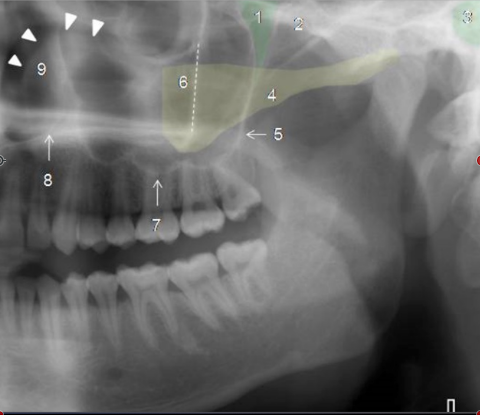

Identify The Structures On The Maxillary, Temporal & Zygomatic Structures.

Identify The Structures On The Mandible.